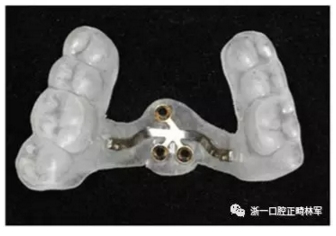

上頜使用3顆微種植釘(2x8mm)固定改良腭板作為骨支抗。安裝過(guò)程如下圖所示。